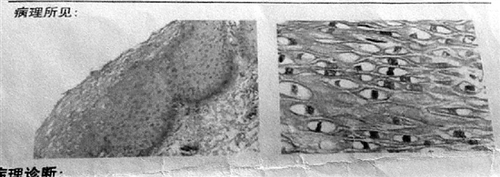

2016年11月10日第一张病理报告

2016年11月24日第二张病理报告

这次阴道镜检查发现HPV亚临床感染,医生建议她做个病理切片。11月8日,病理检查结果出来了,诊断为:低分化癌伴坏死及部分区退变。

当天,医生带着张女士又做了一次病理检查,第二天出具的病理报告上,医生修正了报告:目前肿瘤诊断证据不充分,不予继续治疗,密切随访。